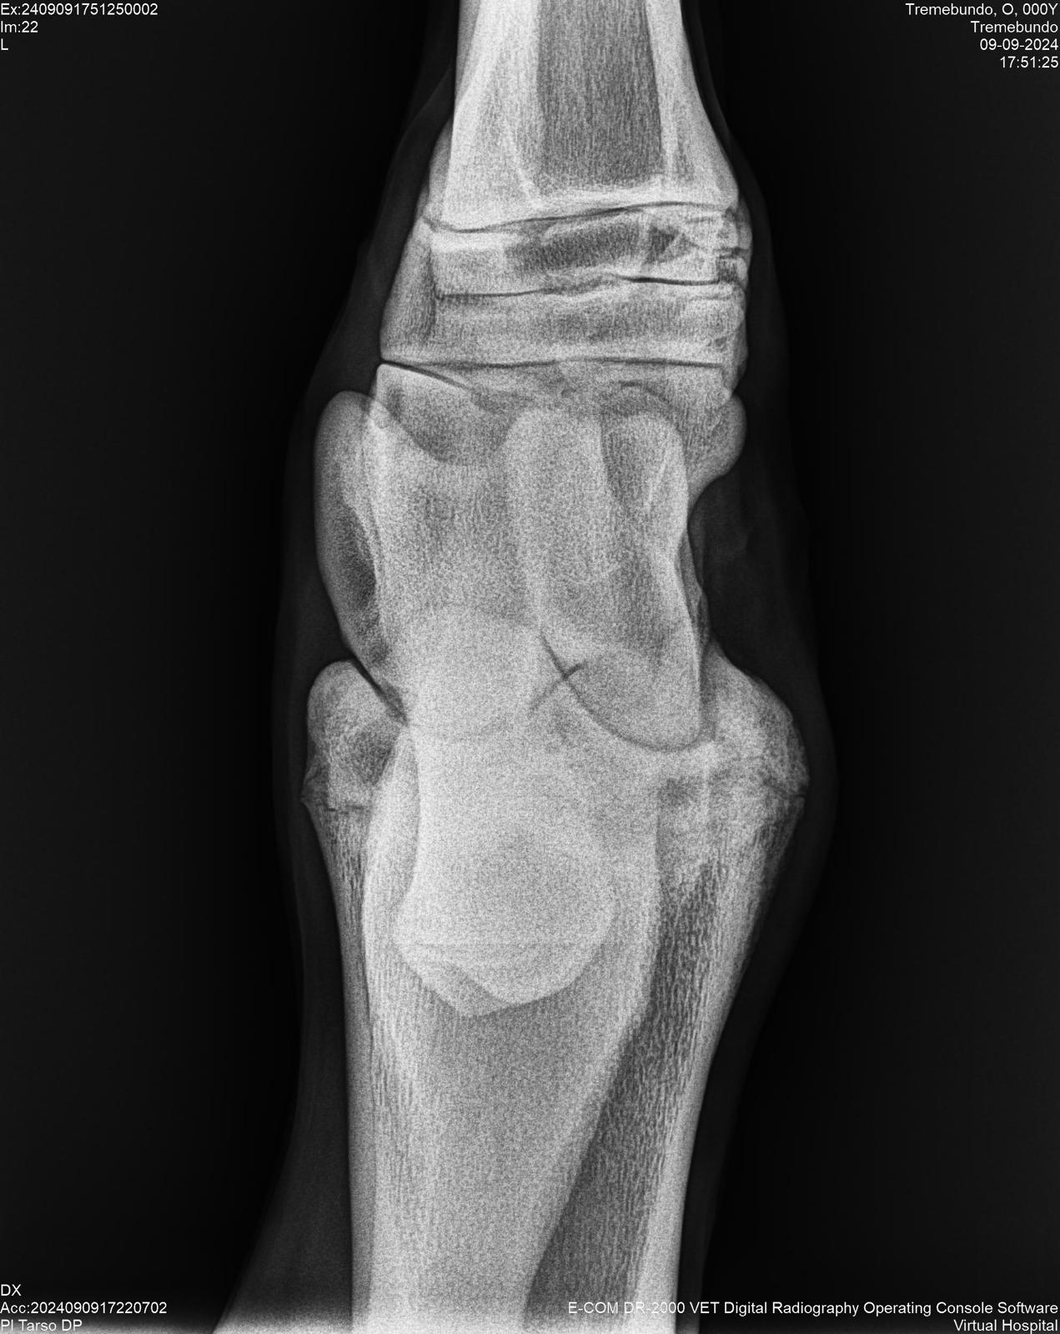

LOTE 37, TREMEBUNDO

Identificador: #291140-

Generacion 2022